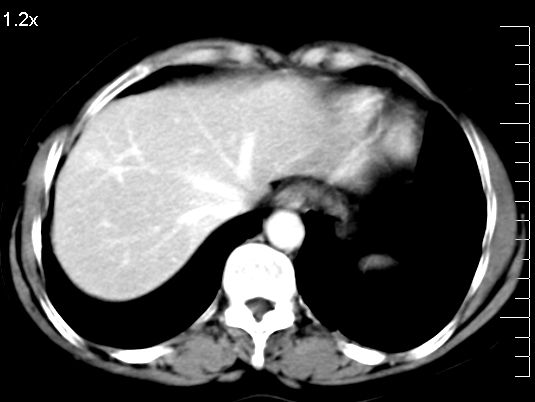

f、52岁,反复上腹部疼痛2年。肺结核病史10多年,胸片双上肺结核纤维化。

ct表现:

肝大小形态未见异常,肝内外胆管无扩张,肝s8段见一动脉期明显血管样强化结节,门脉期呈高密度,延迟期呈等密度,胆囊不大,增强扫描见胆囊及胆囊颈管壁增厚,有强化。

双肾灌注良好,代谢增快,动脉期肾盂见造影剂,左肾下极背侧见一略低密度病灶,延迟期见似不强化囊肿,双侧肾上腺未见异常。

胰腺及脾未见异常。肾门水平腹膜后见小淋巴结。腹腔未见积液征象。